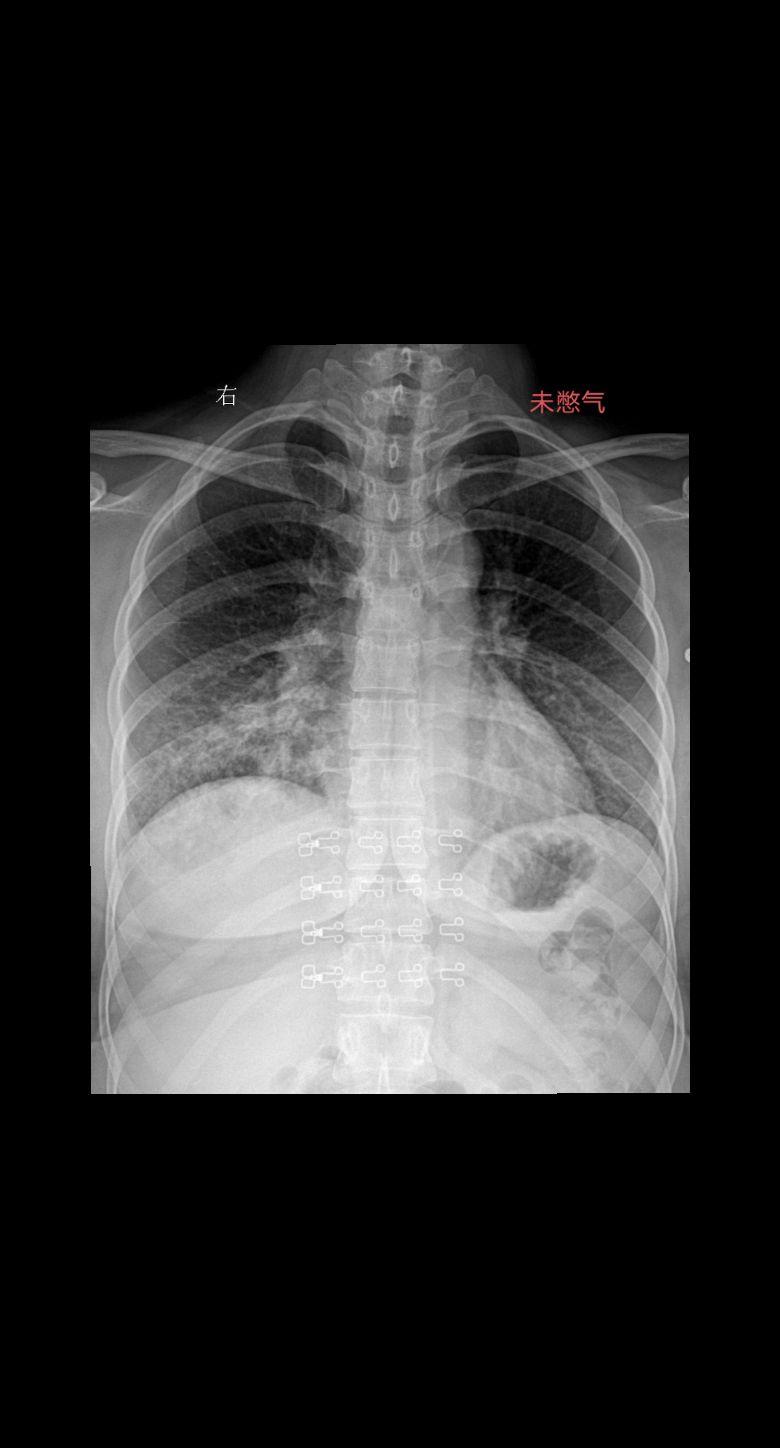

家人们你们拍胸片的时候让患者深呼吸憋气吗 患者主诉咳嗽感冒一周29岁女